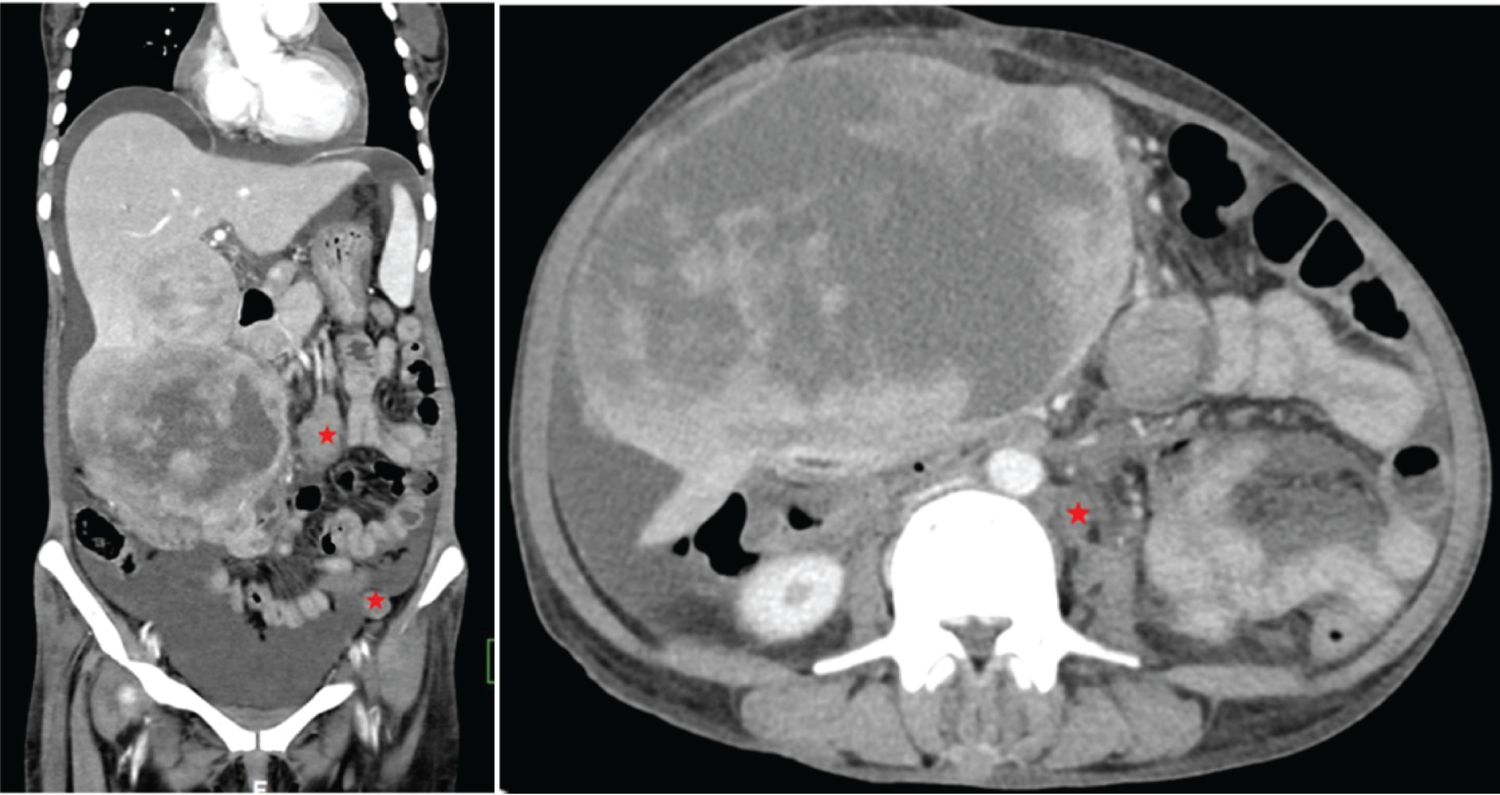

Our patient is a middle aged female who is a known case of Neurofibromatosis type 1 and undergone MRI spine to look for nerve sheath tumours. Liver lesion was incidentally found out during imaging. CECT shows a large, irregular lobulated soft tissue dense lesion in perivascular distribution with preservation of the vessels showing no significant enhancement in the epigastric region involving the left lobe of liver. MRI shows heterogeneous predominantly T2 hyperintense macro nodular lesion involving the left lobe of liver (Figure 3).

Figure 3: Plexiform NF of liver. (a,b) Contrast enhanced CT axial sections shows a large, irregular lobulated soft tissue dense lesion in perivascular distribution with preservation of the vessels showing no significant enhancement in epigastric region involving the left lobe of liver. Left branch of portal vein not separately made out, possibly thrombosed. Left branch of hepatic artery seen coursing through the lesion. Lesion abuts the lesser curvature of stomach, pancreas and spleen with no obvious infiltration. (c) Small soft tissue dense nodular lesion seen in the subcutaneous plane of anterior abdominal wall ( ↧ ); (d,e) MRI-T2 axial (a) and T2 HASTE (b) coronal sections shows heterogeneous predominantly T2 hyperintense macro nodular lesion involving the left lobe of liver. Flow voids of left branch of portal vein not seen, suggestive of thrombosis. View Figure 3